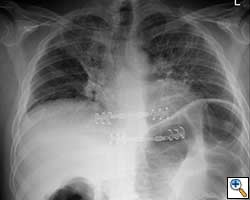

- Chest wall resection for malignancy (Figures 4-5)

| Figure 4: Model showing application in chest wall resection. | Figure 5: Postoperative chest x-ray showing the implants |